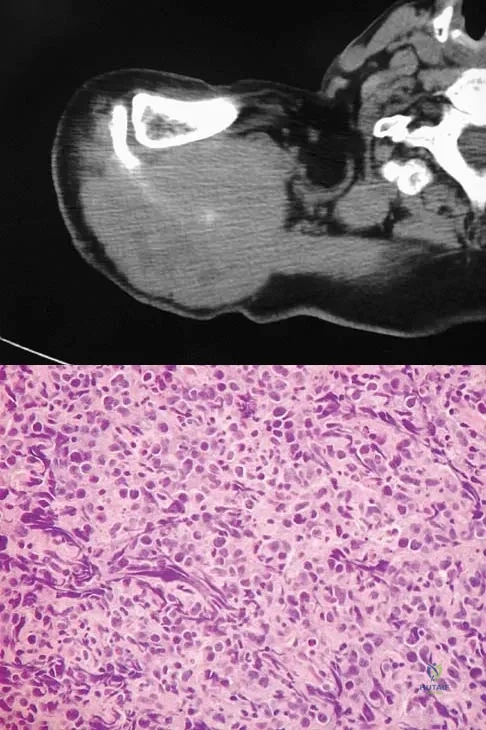

Question 6

A 43-year-old man has had right groin pain for the past 3 months. A radiograph, CT scan, and biopsy specimen are shown in Figures 18a through 18c. What is the most likely diagnosis?

Explanation